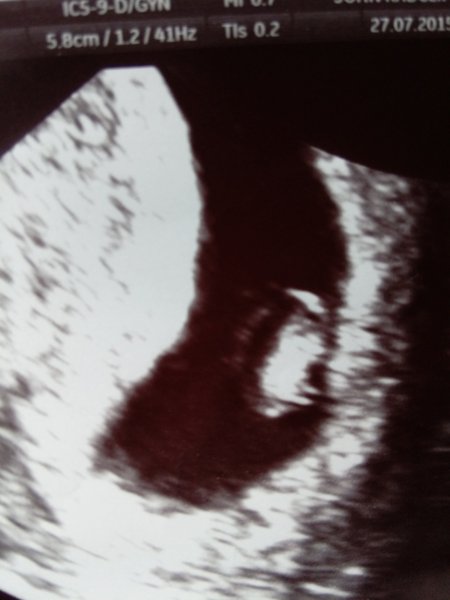

celen, here's my scan from yesterday at 7+4. You can't see a lot and I think it still has a tail! I think those are its little leggies at the bottom Smile

Had my early scan today and there's a 17 mm blob with a heartbeat in there Smile I though I was 8+4 but dr said 8+0 according to measurement, but the uncertainty in the measurement is plus/minus 6 days so I won't worry about that.

Just amazed that there is someone in there with his/her own beating heart! Made it feel a little bit more real.